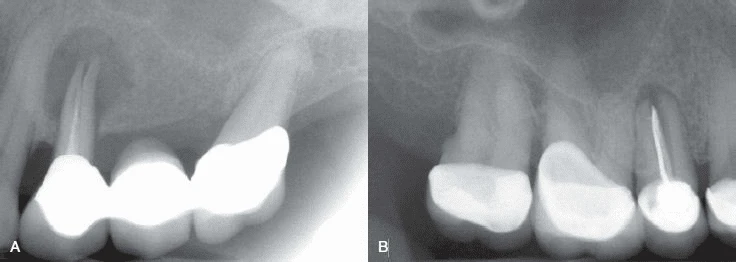

Thông thường khi một răng chết tuỷ thì hình ảnh X quang của nó sẽ thay đổi, mất xương xảy ra ở vùng chóp. Tuy nhiên, khi một răng bị nứt dọc hoặc chia chân răng, vùng mất xương có khuynh hướng cho hình ảnh “vòng sáng”, thấu quang xung quanh chân răng. Vùng thấu quang cũng có thể đi dọc toàn bộ một bên chân răng và thường được gọi là tổn thương “dạng chữ J”.

Hình 13. Hình ảnh tiêu xương “dạng chữ J”

- Hình 14. Tiêu xương rộng khu trú quanh một răng, những răng cạnh đó bình thường, gợi ý một trường hợp nứt dọc chân răng

Hình 15. Khi răng có ống tuỷ rộng hơn so với răng cùng loại hoặc so với răng cạnh nó thì nên nghi ngờ có nứt dọc chân răng

Hình 16. Khi có khoảng trống giữa chất trám bít ống tuỷ và thành ống tuỷ thì nghi ngờ cao có chia chân răng.